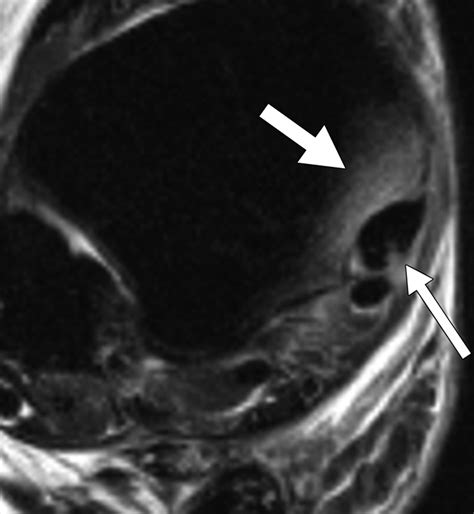

Magnetic Resonance Imaging (MRI) Offers detailed images of the bone marrow and surrounding tissues, making it the gold standard for diagnosing bone marrow edema.